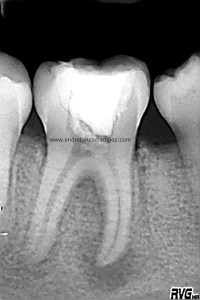

Bueno, pues hoy voy a poner un casito de otro molar inferior, un 4.6, de un chico de unos 14 años. Presentaba una necrosis con una lesión periodontal

Cuando tratamos a niños, tenemos que entender que en muchas ocasiones los conductos no se han cerrado formando sistemas de conductos muy difíciles de limpiar tanto química como mecánicamente. Es este caso, presentaba un istmo mesial acintado que lo tratamos como si tuviese varios conductos. Colocamos H de Ca, soy ,en ciertos casos, un defensor del medicamento intraconductos, con lo que lo hicimos en  dos sesiones.

Una vez que hemos limpiado los conductos con un sistema de instrumentación  Protaper en combinación con limas K3. Pasamos a obturar los mismos con una técnica de condensación vertical de ola contínua de Buchanan y un backfilling con la gutapercha inyectada de la pistola ObturaII. Tomamos varias proyecciones, orto-mesio-distal